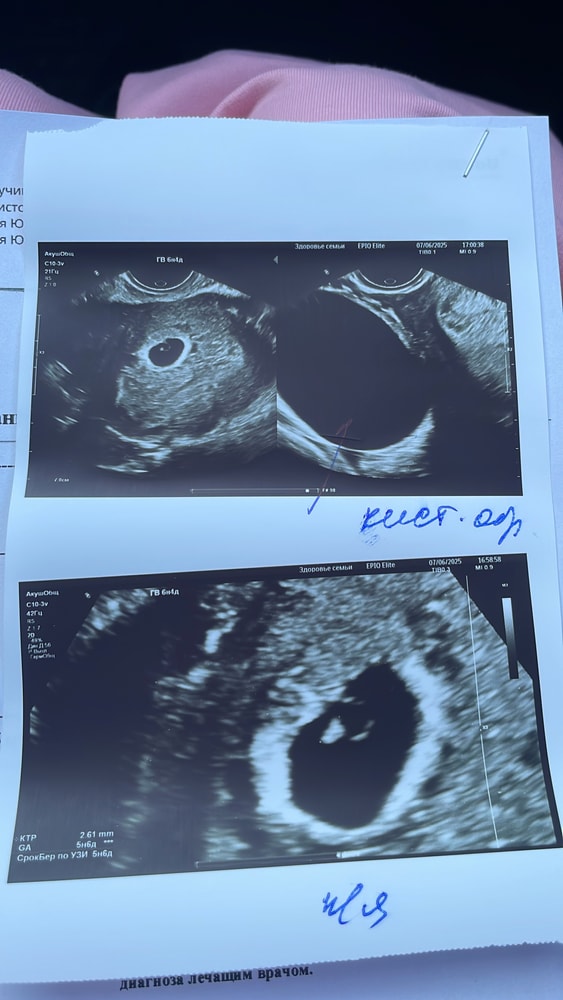

Узи, фолликулометрияНеделю назад по УЗИ всё было хорошо, доминантный фолликул 21 мм. Сегодня прихожу на очередное УЗИ, узнать, была ли овуляция, и узнаю, что в обоих яичниках кисты, овуляции не было( Фото УЗИ прикрепила. Не мог врач ничего перепутать? Может быть есть тут врачи..

Киста вроде как БОЛЬШЕ даже того фолликула, что рос.

KITI, у меня которая сверху 45 см, снизу 25 см. ХГЧ не колола. Прогик каждый месяц за 30, овуляция есть в каждом цикле, за редким исключением

Ксеня, вот у меня 45 см сейчас. самое интересное, что врач сказала "беременности вроде нет, и вроде не жёлтое тело". жидкость в позадиматочном пространстве присутствует